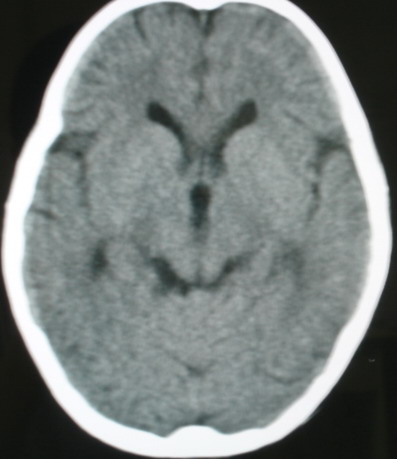

m/8y/,右侧眼睑下垂数日,发育良好,无外伤史,无头痛、恶心、呕吐,学习成绩良好。

ct意见:1、颅内血管畸形。2、右侧海绵窦血管瘤(颈内动脉海绵窦段动脉瘤)。3、脑萎缩。4、建议mr或dsa.

增强片

海绵窦瘘.注意眶内静脉有扩张.

右侧海绵窦血管瘤伴右侧海绵窦漏形成(由于右眼上静脉较左侧增粗。故考虑)。

支持 右侧颈内动脉海绵窦瘘.注意眶内静脉有扩张.